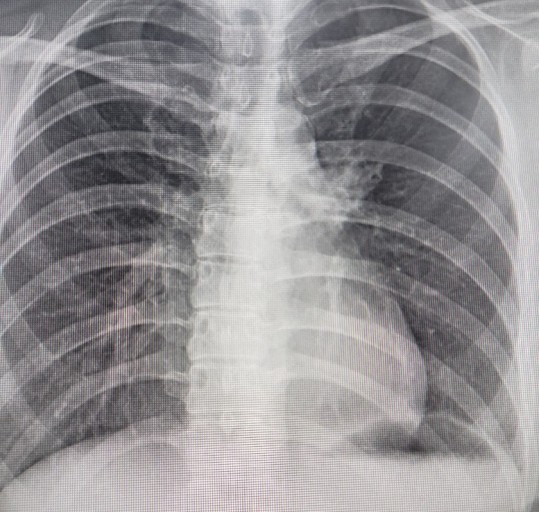

폐암은 위암, 갑상선암 다음으로 3번째로 발병 빈도가 높은 3대 암 중 한 가지입니다. 폐암은 재발과 전이까지의 빈도도 잦은지라 완치가 어렵다고 하며 폐암 발병 초기에는 거의 증상이 없을 수가 있어 수술이 불가능한 3기, 혹은 4기에 주로 진단된다고 합니다.

폐암 4기에 이르게 되면 5년 생존률이 30% 대로 떨어지게 된다고 합니다. 그리해서 폐암은 암 질병이자 중 사망자 비율이 가장 높은 것으로 나타나고 있습니다.

폐암은 사망률 2위를 차지하고 있는 간암에 비해 무려 2배에 가까운 사망률을 보이고 있다고 해요. 이렇게 치명적인 폐암에 대해 미리 알고 대처하는 것이 바람직할 것 같습니다. 아래에서는 폐암이라 판단해 볼 수 있는 그 초기증상에 대해 간단히 설명드리겠습니다.